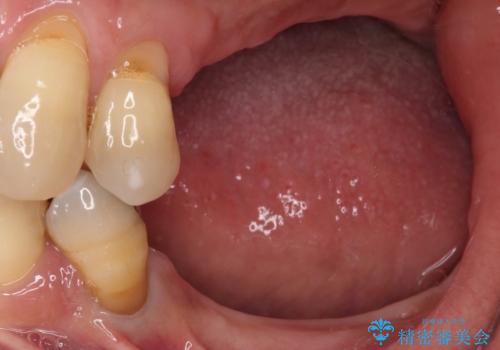

- 以前入れ歯を製作したものの、装着感が悪く使用できなかったとのことで来院された患者様です。

インプラントによる治療プランも提案しましたが、インプラントは避けたいとのご希望であったため、入れ歯による補綴治療を行うこととしました。

自費治療の義歯は装着感がとても良いですが、急に入れ歯を装着すると、異物感が強く継続使用できなくなるため、仮歯の期間中に保険治療での義歯を装着してもらい、口腔内を義歯に慣れさせるようにしました。